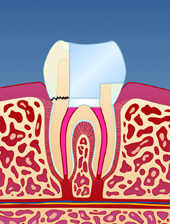

En rotfylt tann er ofte svekket på grunn av store fyllinger og lite gjenværende tannsubstans (fig. I). Som resultat vil en rotfylt tann være mer utsatt for å knekke enn en tann som ikke er rotfylt (fig. II-III). Dersom rotfyllingen blir utsatt for lekkasje over lengre tid, kan bakterier komme til og lage en ny infeksjon i den rotfylte tannen (fig. IV). Der er derfor viktig å kontakte tannlege snarest dersom deler av en rotfylt tann knekker av.

| figur I | | figur II | | figur III | | figur IV |